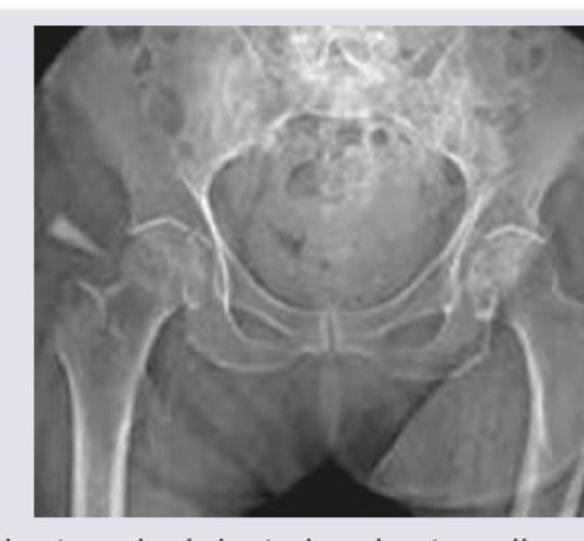

Question 3: An elderly patient slipped in the bathroom and sustained injury over the hip joint. X- Ray is shown below. Her attitude of leg will be?

- A. Shortened, abducted and externally rotated (Correct Answer)

- B. Shortened and abducted

- C. Lengthened and internally rotated

- D. Flexed and adducted and internally rotated

Explanation: ***Shortened, abducted and externally rotated*** - The X-ray image reveals an **intertrochanteric fracture** of the right hip, characterized by a fracture line between the greater and lesser trochanters. - Due to the pull of strong muscles acting on the fractured fragments (e.g., iliopsoas, gluteal muscles), the limb typically assumes a position of **shortening, abduction, and external rotation**. *Shortened and abducted* - While **shortening** and **abduction** are present in intertrochanteric fractures, this answer is incomplete as it misses the crucial component of **external rotation**. - The powerful **external rotators** and the **gravity** acting on the unstable distal fragment contribute significantly to the external rotation. *Lengthened and internally rotated* - This attitude is characteristic of a **posterior hip dislocation**, where the femoral head is driven posteriorly and superiorly, typically leading to limb lengthening and internal rotation. - This is opposite to the typical presentation of an intertrochanteric fracture as seen in the X-ray. *Flexed and adducted and internally rotated* - A flexed, adducted, and internally rotated position is also seen in **posterior hip dislocations**, which is not consistent with the X-ray findings of an intertrochanteric hip fracture. - Hip fractures usually result in some degree of **external rotation** due to the muscle forces.